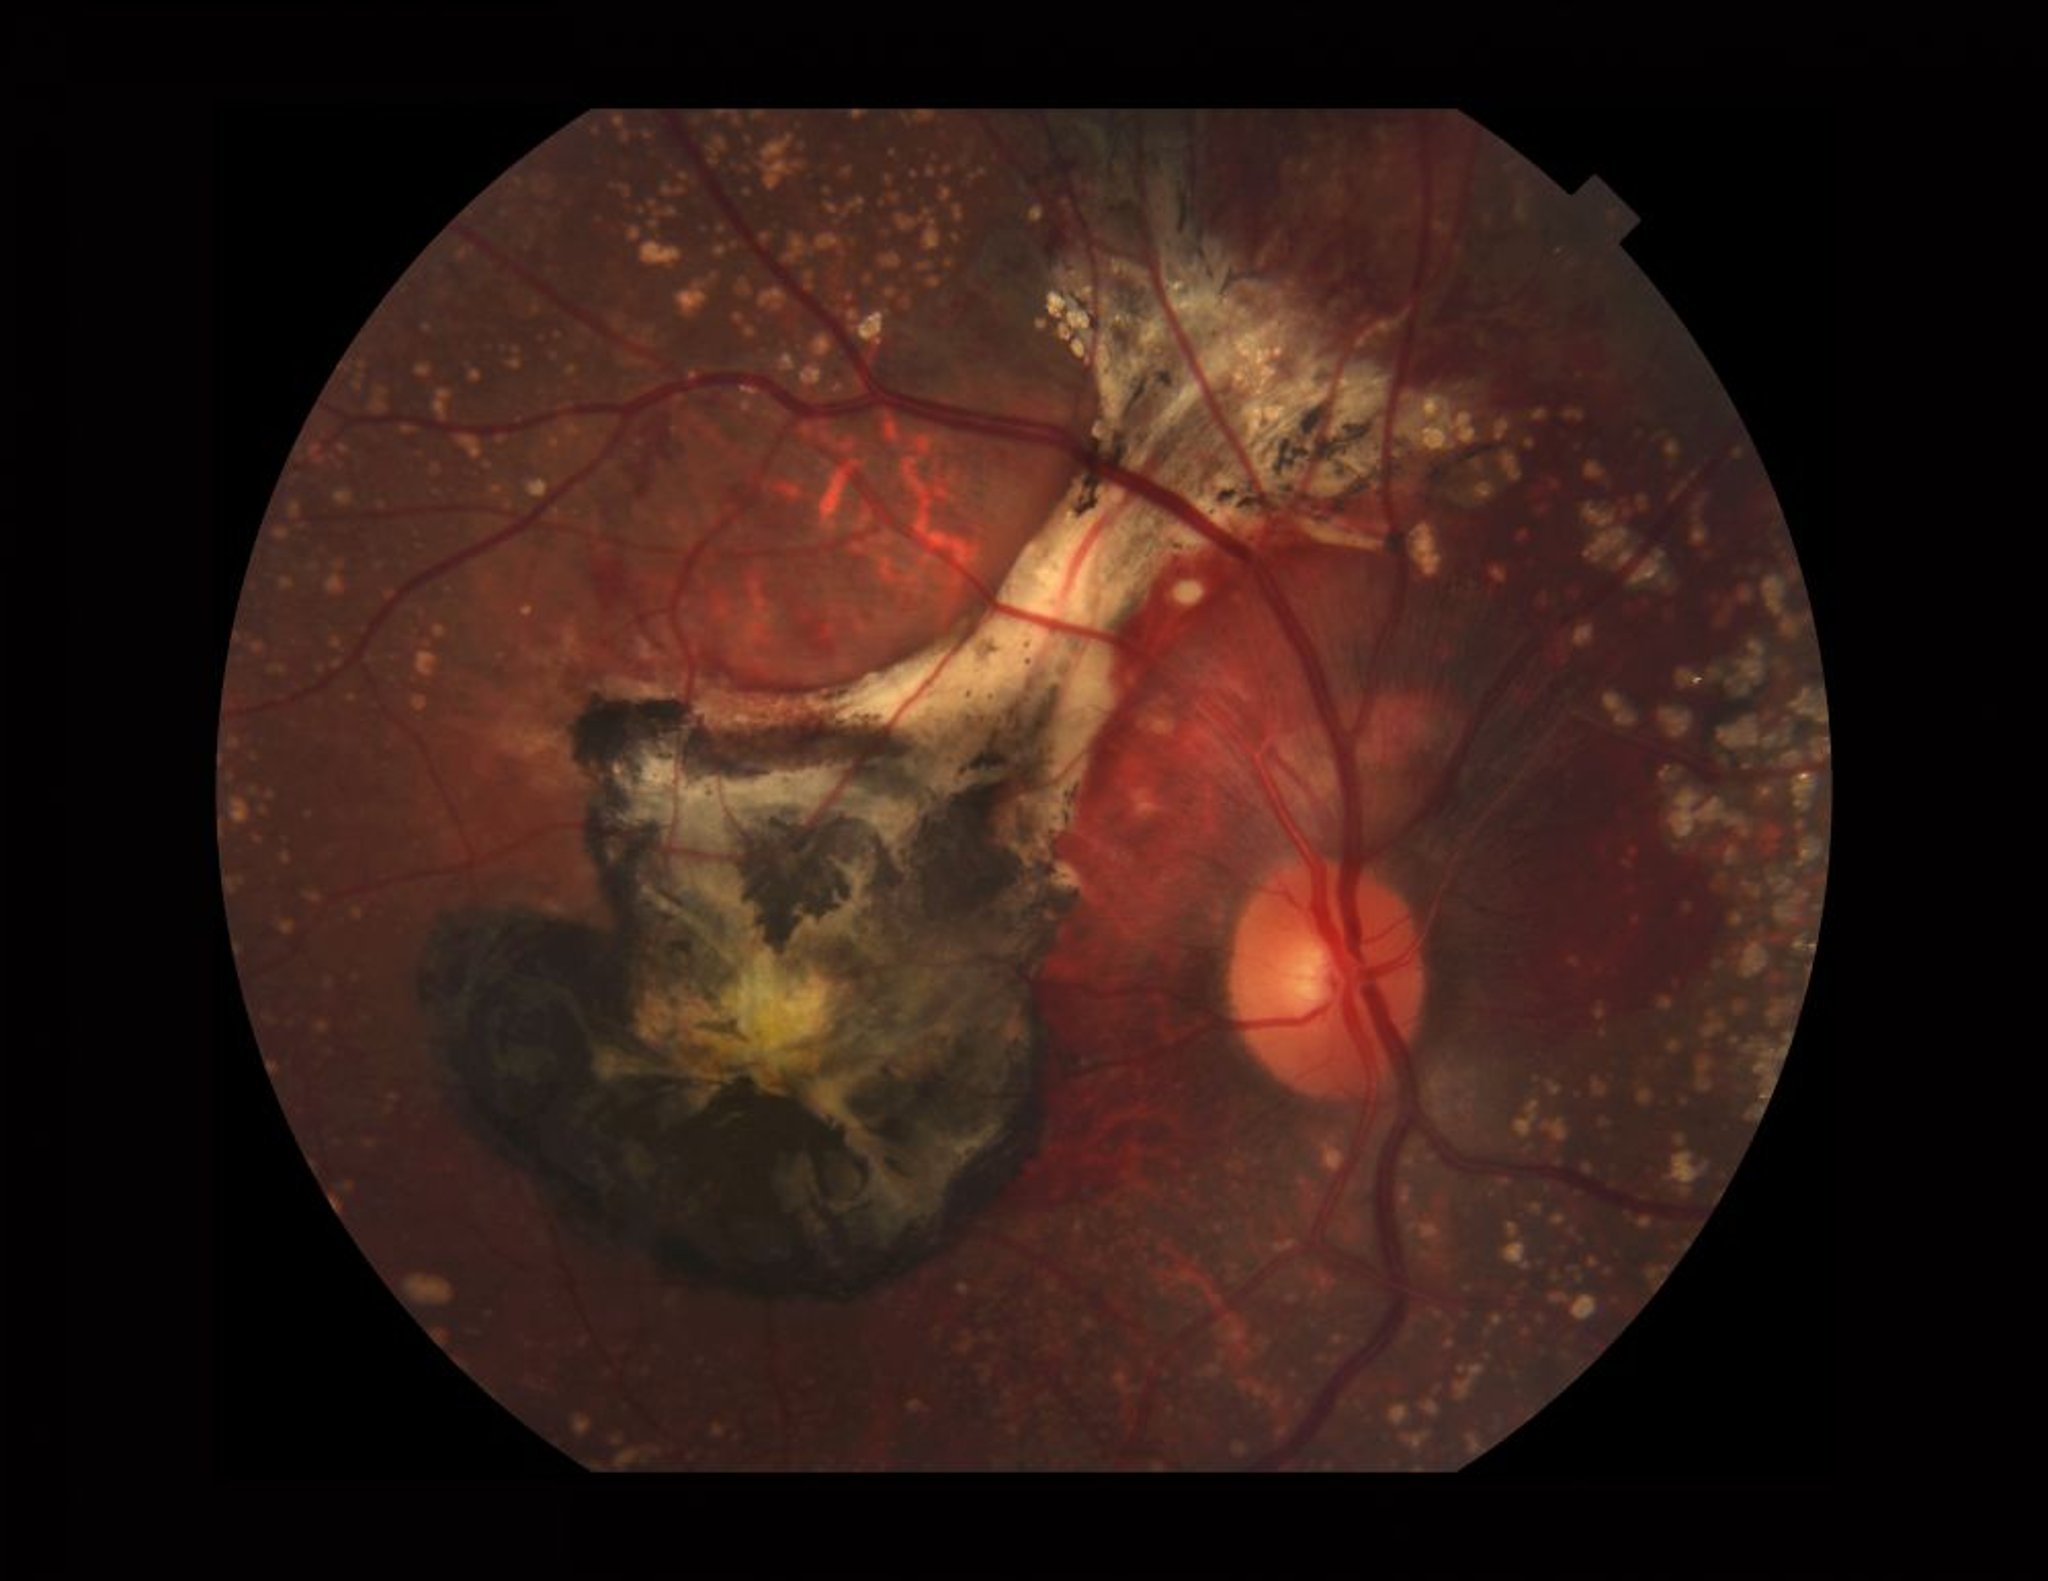

Возрастная макулярная дегенерация (влажная форма)

Фотография сетчатки, пораженной влажной формой ВМД. На данном изображении показаны кальцинированные друзы, субретинальное кровотечение, хориоидальная неоваскулярная мембрана (черная от застарелой крови и фиброза) и пятна пигмента ксантофилла (желтый цвет).

PAUL WHITTEN/SCIENCE PHOTO LIBRARY